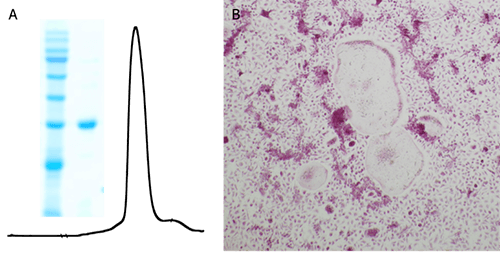

Measured by its ability to induce osteoclast differentiation of RAW 264.7 mouse monocyte/macrophage cells. The ED50 for this effect is 50ng/mL.

Purity:Greater than 95.0% as determined by: (a) Analysis by RP-HPLC. (b) Analysis by SDS-PAGE.

A. The size-exclusion chromatography of recombinant mouse RANKL and the SDS-PAGE analysis. B. The bone marrow-derived monocytes were cultured in the presence of M-CSF(25 ng/ml, (Cat. No. LT13501)) and RANKL (50 ng/ml) for 6 days. The cells were then fixed with 4% PFA and stained by the TRAP solution. The image showed the formation of big multiple nucleus TRAP-positive osteoclasts formed after M-CSF and RANKL stimulation.